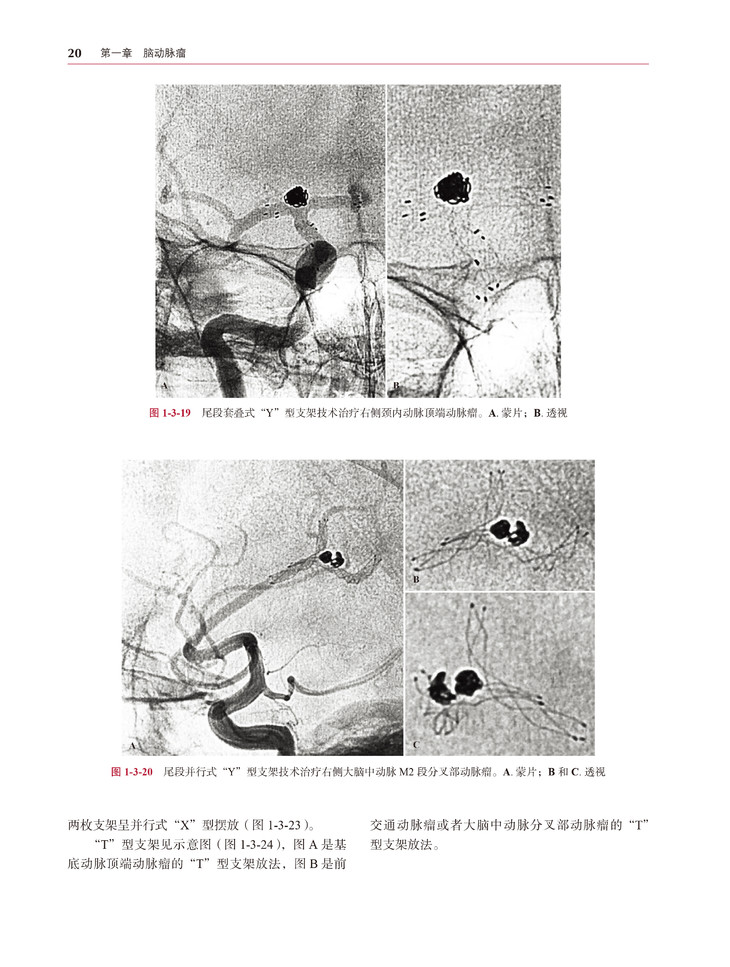

本书是一本介绍神经介入治疗相关病例的专业书籍,作者都是来自神经介入领域的知名专家。本书所选择的病例范围广泛并且具有代表性,共包括脑动脉瘤、脑血管畸形、脑血管急性闭塞、脑血管慢性狭窄及闭塞、特殊病例五个部分。所有病例均有相应介绍,包括患者的临床表现、影像学检查、手术操作、病例讨论等。

本书作者们通过丰富的实践经验和理论知识,对病例及手术治疗进行了生动介绍。书中包含了大量的影像图片和插图,能够为读者直观地呈现病